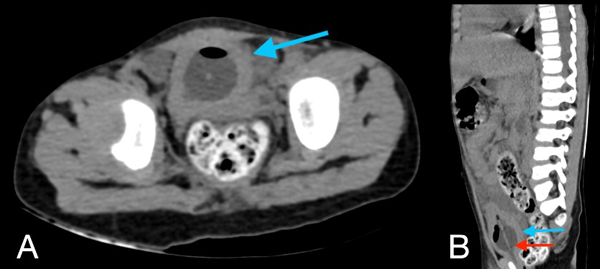

En la tomografía se evidenció presencia de S1-S2 con ausencia del resto de cuerpos sacro-coxígeos, así como hipodensidad a nivel de la médula que podría sugerir siringomielia (Figura 1). También se encontró falta de unión de algunos elementos posteriores a nivel de L5-S1 (Figura 2), lo que sugiere el diagnóstico de síndrome de regresión caudal asociado a probable siringomielia y probable vejiga neurogénica dado engrosamiento marcado de las paredes vesicales (Figura 3). Además, se encontró dilatación ureteropielocalicial de forma bilateral (Figura 4). A raíz de estos hallazgos, se solicitó una valoración por genética clínica, la cual determinó que la paciente cumple con los criterios clínicos de regresión caudal y tiene antecedentes de diabetes gestacional insulino-dependiente, lo cual es un factor de riesgo.

Figura 4. Tomografía de abdomen en corte axial (A) y sagital (B): la vejiga evidencia engrosamiento concéntrico de sus paredes de aproximadamente 7,4 mm (flecha azul en A y B), con la presencia de balón de sonda Foley en su interior (flecha roja en B).

En este caso, se encontró una ausencia parcial sacro coxígea con preservación de S1 (Figura 1), asociada a no unión de elementos posteriores de L5 y S1 (Figura 2), siendo un síndrome de regresión caudal tipo I según Pang, asociado a alteraciones genitourinarias dadas por hidronefrosis bilateral (Figura 3) y engrosamiento de las paredes vesicales (Figura 4).